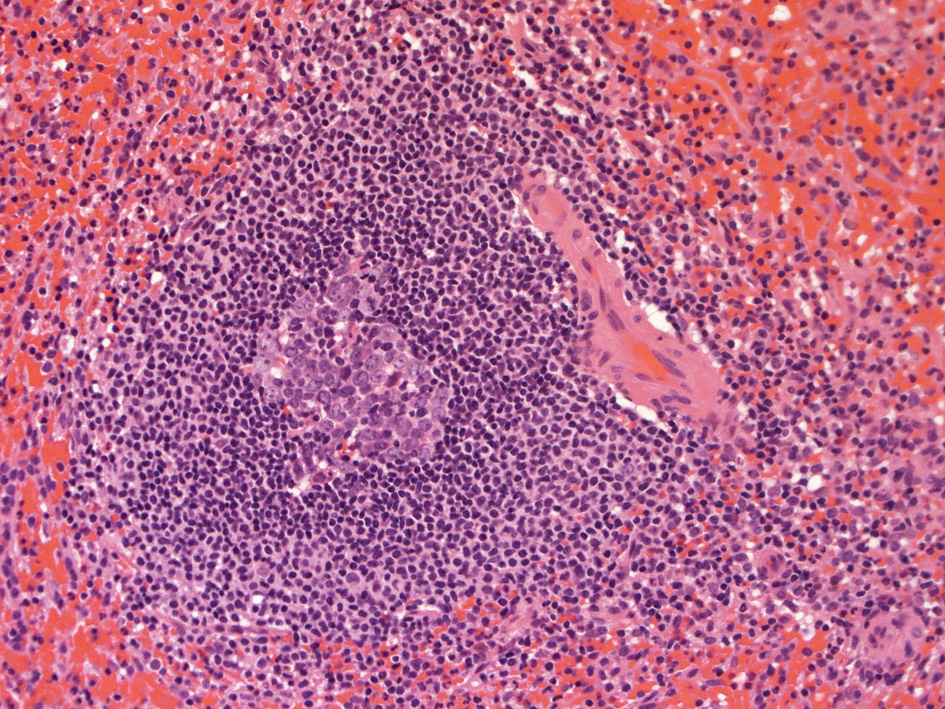

spleenA011.jpg

白脾髄, 辺縁帯/周辺帯は脾臓のリンパ装置として機能する. 開放性末梢血管流床を介して伝達される免疫情報はこれらのリンパ装置で処理され効率よく免疫反応がおこる.

白脾髄 white pulpは中心動脈周囲に形成されているリンパ組織で, 動脈周囲リンパ鞘 periarteriolar lymphoid sheath(PALS)とリンパ濾胞(lymph follicles)の異なる2つの領域が識別される.

脾動脈脾柱という結合組織を通って実質内に入るところから毛細血管に至るところまで、その周囲にリンパ鞘(リンパ鞘=PALS/ peri-arterial lymphatic sheathの略)が形成され、所々にリンパ濾胞が発達している. 濾胞内には胚中心が見られることが多い。胚中心の周りには暗調にそまる小型のリンパ球がマントル層を作って取り囲む。リンパ鞘もリンパ節の構造と同じく粗で不規則な細網線維からできたネットワークが骨格となっている。

リンパ鞘はT細胞領域リンパ濾胞はB細胞由来です。PALSのT-cellsはCD4+ cell > CD8+ T-cells

脾臓の辺縁帯は通常,よく発達した濾胞周囲領域であり,そろった/一様な核と一定量の透明な細胞質を持つ中型のリンパ球からなり,芽球が散在している。

胚中心が多数出現しているときはなんらかの抗原刺激を受けたと考えられる.

慢性感染症がある人の脾臓や特発性血小板減少性紫斑病の人の脾臓では胚中心が特に発達している. 一方で自己免疫性溶血性貧血では胚中心は少なく、先天性球状赤血球症ではほとんど見られない.